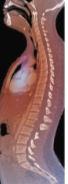

Spinal column develops an ___-shape as infant grows

s

Primary curvatures

thoracic and sacral curves present during fetal period

Secondary curvatures

Cervical curvature - allows us to hold our heads up

Lumbar curvature - shifts weight of body onto sacrum

Scoliosis

lateral curvatures in vertebral column

exaggerated cervical and lumbar curvatures

Lordosis (swayback)

Kyphosis (hunchback)

exaggeration of thoracic curvature

Lordosis

Kyphosis